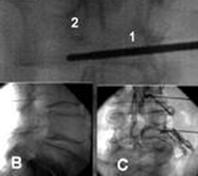

En nuestro caso todos los bloqueos radiculares selectivos (BRS) se efectúan con control radiológico, en quirófano, en régimen ambulatorio y con sedación consciente. Se los considera bloqueos diagnósticos que se realizan antes de un tratamiento definitivo, ya sea quirúrgico o bien intervencionista (radiofrecuencia pulsada). Las indicaciones para realizar un BRS son el dolor radicular, independientemente de su origen (herniación del núcleo pulposo, estenosis de canal, síndrome poslaminectomía).

Bloqueo radicular selectivo lumbar

El ganglio de la raíz dorsal está situado en la parte superior del agujero intervertebral, justo debajo del pedículo; en las raíces superiores está situado más dorsalmente que el de las inferiores y esto es consecuencia de las diferentes direcciones que toman las raíces al salir del agujero intervertebral. En la región lumbar la posición del ganglio dentro del canal radicular es variable.